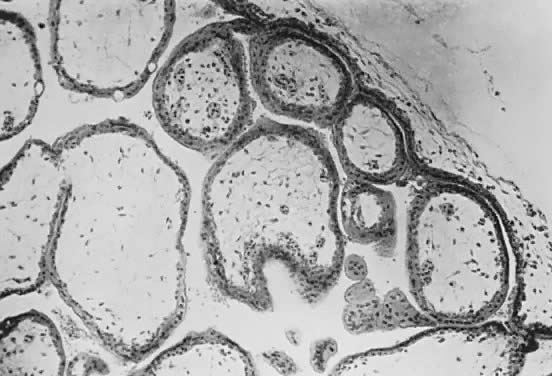

The trophoblast has two layers: the cytotrophoblast and the syncytiotrophoblast. Syncytiotrophoblast is formed from the underlying cytotrophoblast. In the first part of pregnancy, these two layers usually are quite distinct on microscopic examination and can be used to date a placenta or pregnancy. Fetal vessels with nucleated fetal red blood cells appear at 21 days' gestation. Thus, the presence of both trophoblast cell layers in the absence of vessels indicates a pregnancy of <21 days. Fetal vessels and red blood cells, along with two cell layers of trophoblast, indicate a pregnancy of 21 days to 5 months (see Fig. 3). After the fifth month of pregnancy, the cytotrophoblast, when viewed under a light microscope, appears to degenerate. Electron microscopic studies have revealed that although the cytotrophoblast becomes thinner, it remains throughout pregnancy, and all syncytial cells formed during the latter half of pregnancy are formed from cytotrophoblast, as in the first portion of gestation. The apparent absence of cytotrophoblast signifies a pregnancy beyond 5 months (Fig. 7). Toward term, the mesenchymal core of each villus becomes more dense and compact, and the fetal vessels appear to be much closer to the overlying syncytiotrophoblast, possibly facilitating transfer of nutrients or waste products. These changes, combined with fibrin deposition within the intervillous space and occasional syncytial knots, are characteristic of a term placenta. At term, the human placenta weighs approximately 500 g.

Fig. 7. Term human placenta. Trophoblast cell layers are less distinct, and syncytial cells are frequently in several layers. (UKMC, ×120)